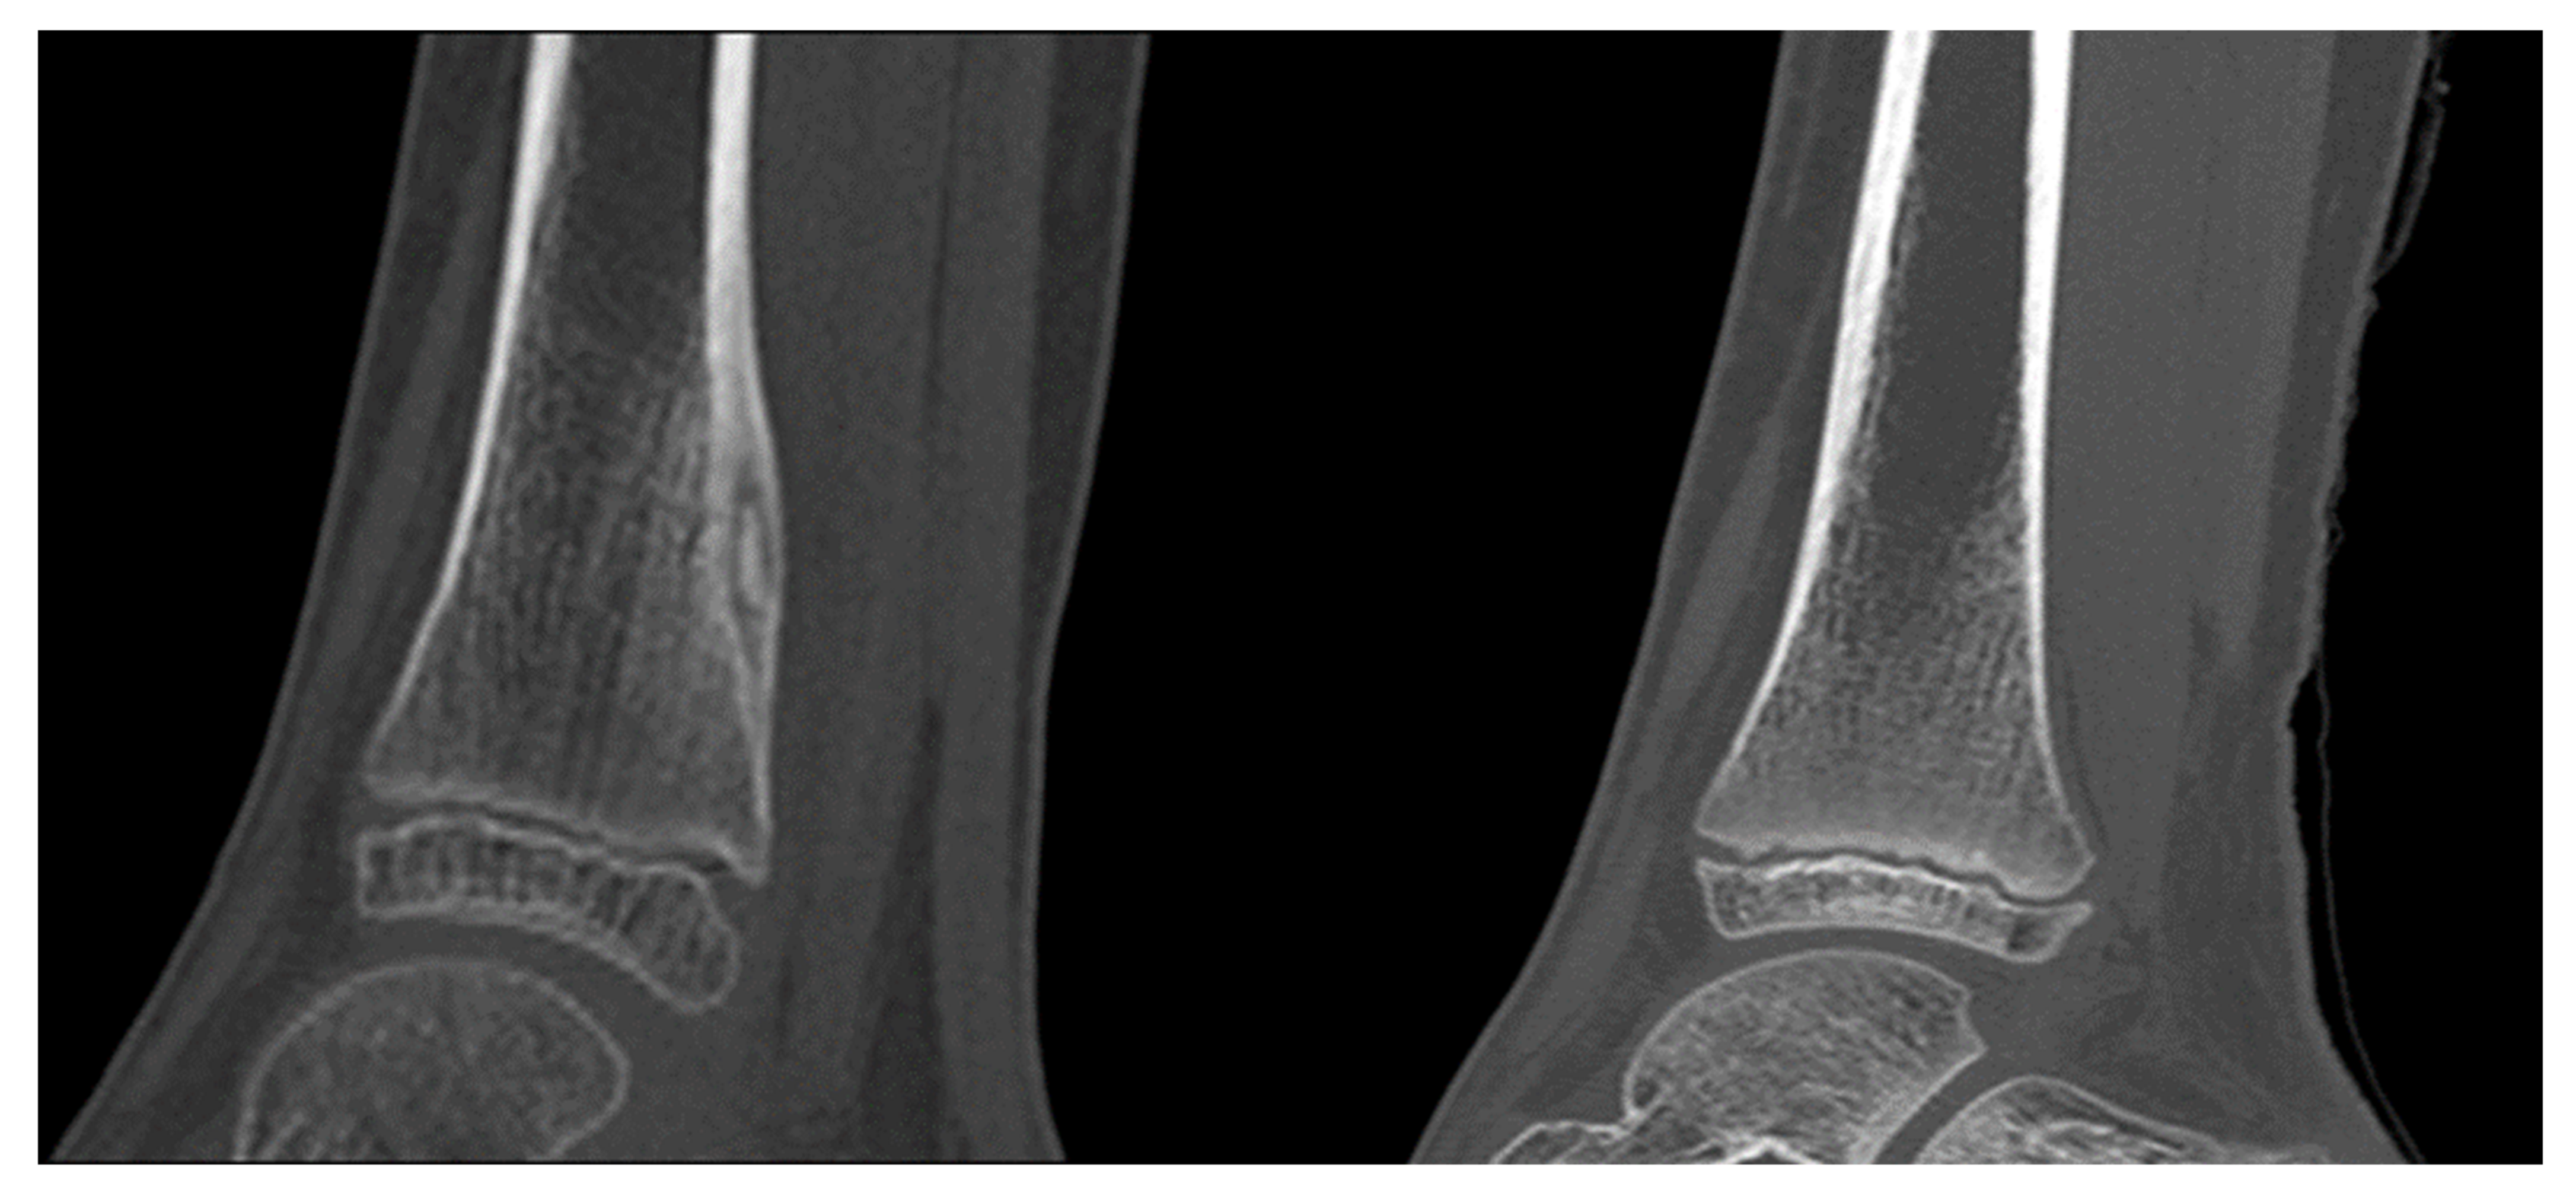

3. Results